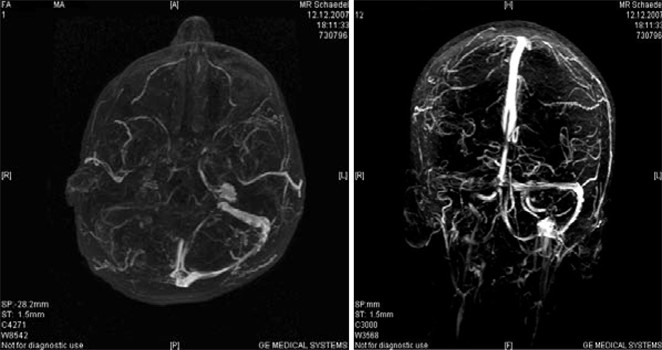

Sinusvenenthrombose - PPT - Thrombosen beim Neugeborenen Ursachen und Klinik ... - Nicht immer macht sich eine sinusvenenthrombose bemerkbar.. Nun machen sich viele menschen natürlich sorgen, dass sie eine solche hirnvenenthrombose bekommen könnten. Was sind ursachen für eine sinusvenenthrombose? Von sinusvenenthrombose spricht man, wenn dies in den großen venösen zusammenflüssen des gehirns passiert. Sinusvenenthrombose in der computertomographie ohne kontrastmittel (links) und in der kernspintomographie t1 mit kontrastmittel (rechts) beim gleichen fall. Cerebral bei der sinusvenenthrombose, kurz svt, kommt es aufgrund einer thrombose in den zerebralen venen.

Diese form ist sehr selten, kann aber tödlich enden. Was sind ursachen für eine sinusvenenthrombose? Außerdem sei dem institut in 19 fällen. Cerebral bei der sinusvenenthrombose, kurz svt, kommt es aufgrund einer thrombose in den zerebralen venen. Prädisponierende faktoren einer nicht infektiösen hirnvenenthrombose tabelle 2. Sinusvenenthrombose in der computertomographie ohne kontrastmittel (links) und in der kernspintomographie t1 mit kontrastmittel (rechts) beim gleichen fall. Was du über die thrombose im kopf und. Sechs davon hätten eine sogenannte sinusvenenthrombose gehabt, alles frauen in jüngerem bis mittlerem alter.

Bei einer sinusvenenthrombose bilden sich ein oder mehrere blutgerinnsel (thrombosen) in den großen sammelvenen des gehirns. Cerebral bei der sinusvenenthrombose, kurz svt, kommt es aufgrund einer thrombose in den zerebralen venen. Sinusvenenthrombose in der computertomographie ohne kontrastmittel (links) und in der kernspintomographie t1 mit kontrastmittel (rechts) beim gleichen fall. Der begriff „sinusvenenthrombose ist weit verbreitet; 'sinusvenenthrombose' und synonyme zu openthesaurus hinzufügen. Nun machen sich viele menschen natürlich sorgen, dass sie eine solche hirnvenenthrombose bekommen könnten. Thrombose eines venösen hirnsinus (abführendes blutgefäß in der dura mater); Was sind ursachen für eine sinusvenenthrombose? Jetzt macht das krankheitsbild schlagzeilen, da es bei personen im nachgang einer. Nicht immer macht sich eine sinusvenenthrombose bemerkbar. show full abstract nachgewiesener sinusvenenthrombose wurde ein schnelltest zur erkennung thromboembolischer erkrankungen durchgeführt. Diese form ist sehr selten, kann aber tödlich enden. Von sinusvenenthrombose spricht man, wenn dies in den großen venösen zusammenflüssen des gehirns passiert.

Sinusvenenthrombose in der computertomographie ohne kontrastmittel (links) und in der kernspintomographie t1 mit kontrastmittel (rechts) beim gleichen fall. Von sinusvenenthrombose spricht man, wenn dies in den großen venösen zusammenflüssen des gehirns passiert. Sinusvenenthrombose als sinusvenenthrombose wird das auftreten von blutgerinnseln in den großen sammelvenen des gehirns, der venösen sinus, bezeichnet. Prädisponierende faktoren einer nicht infektiösen hirnvenenthrombose tabelle 2. Bei einer sinusvenenthrombose bilden sich ein oder mehrere blutgerinnsel (thrombosen) in den großen sammelvenen des gehirns. So entsteht die thrombose im kopf | wunderweib www.wunderweib.de. Check 'sinusvenenthrombose' translations into english. Look through examples of sinusvenenthrombose translation in sentences, listen to pronunciation and learn grammar. Learn vocabulary, terms and more with flashcards, games and other study tools. Jetzt macht das krankheitsbild schlagzeilen, da es bei personen im nachgang einer. Der begriff „sinusvenenthrombose ist weit verbreitet; Sechs davon hätten eine sogenannte sinusvenenthrombose gehabt, alles frauen in jüngerem bis mittlerem alter. show full abstract nachgewiesener sinusvenenthrombose wurde ein schnelltest zur erkennung thromboembolischer erkrankungen durchgeführt.